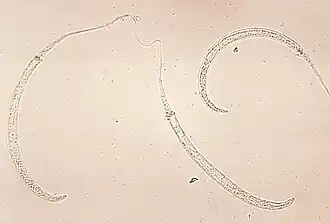

Larven von Dracunculus medinensis, dem Medinawurm | ||||||||||||

Dracunculus (lateinisch dracunculus kleine Schlange, Verkleinerungsform von draco Drache) ist eine Gattung von Fadenwürmern (Nematoden), deren Arten als Parasiten in Gewebe und Körperhöhlen von Reptilien und Säugetieren einschließlich des Menschen vorkommen.